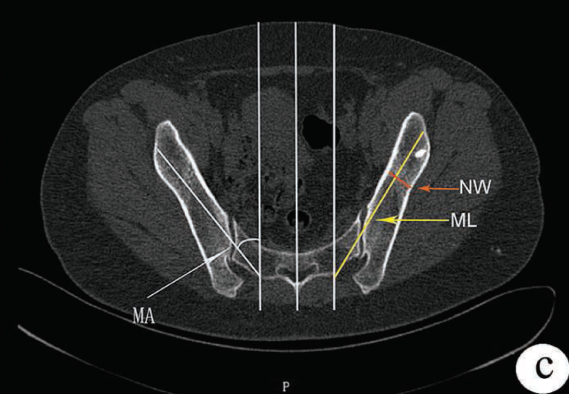

解剖學(xué)上為S1和S2背孔中點(diǎn)的橫向連線,與S1/S2背孔邊緣的縱向連線交點(diǎn)

該點(diǎn)需與S1的椎弓根釘保持對線

3. 置釘角度

方向朝尾端傾斜20-30°;向內(nèi)傾斜40-50°